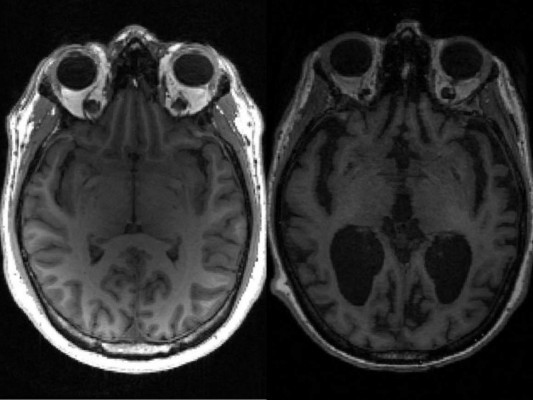

En la enfermedad de Alzheimer, tau y otra proteína llamada beta amiloide se acumulan en nudos y placas -conocidos ambos como agregados- que matan las células cerebrales y encogen el cerebro.

El grado de la enfermedad de Alzheimer se mide según la denominada 'Escala Braak'. El equipo encontró que lleva unos 35 años avanzar desde la etapa tres, cuando comienzan a aparecer síntomas leves, a la etapa seis, que es la más avanzada.

Si los agregados se duplican aproximadamente en cinco años, entonces en 35 años se habrían multiplicado por 128. Ese crecimiento exponencial 'explica porqué la enfermedad demora tanto en desarrollarse y luego la persona se deteriora rápidamente'.